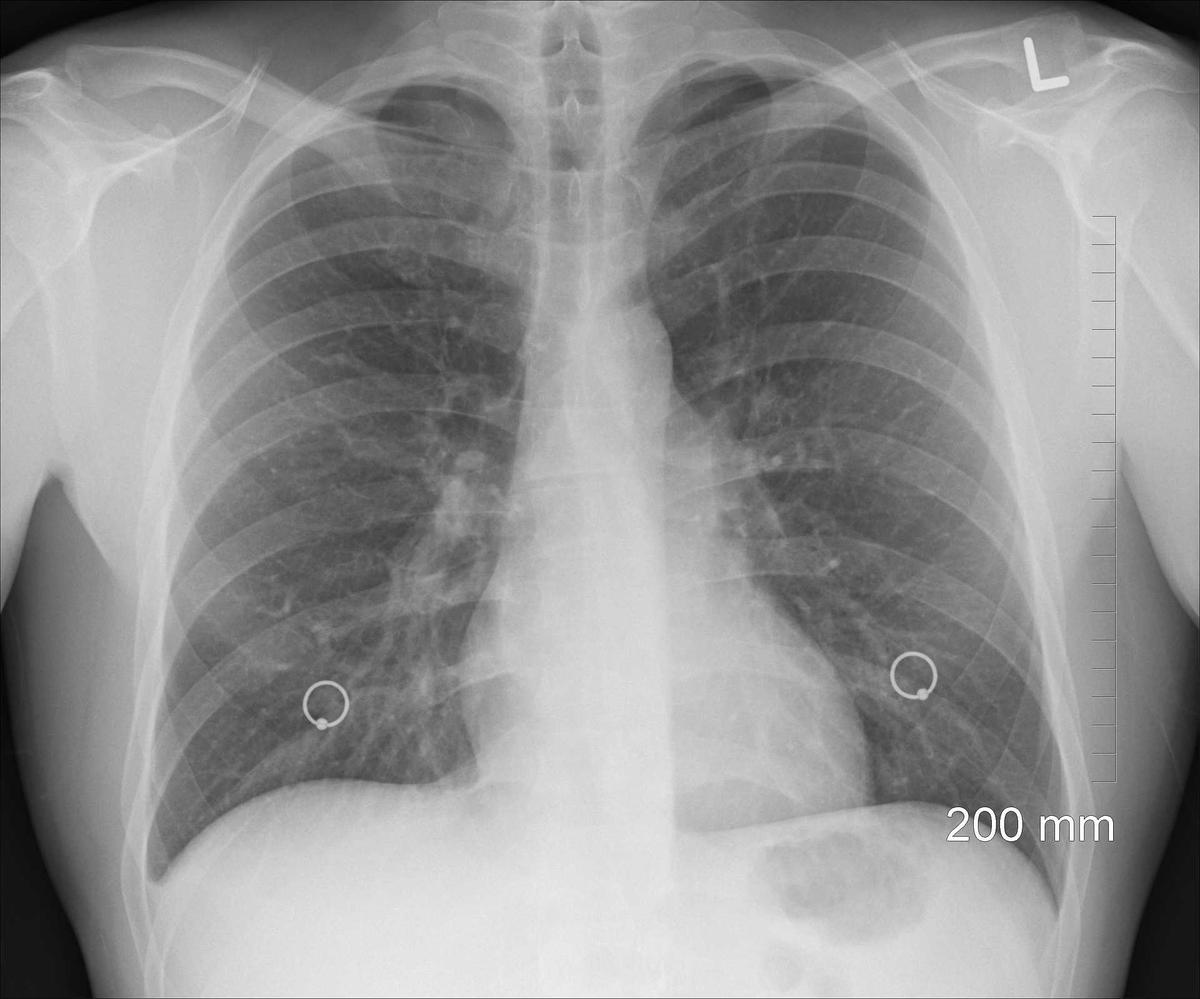

Sementara itu, terkait dengan penanganan pada pasien kanker paru, Erlang mengatakan saat ini penatalaksanaan penanganan kanker paru di Indonesia sudah cukup maju. Penatalaksanaan terbaru untuk membantu menangani pasien kanker paru saat ini, katanya, adalah dengan imunoterapi.